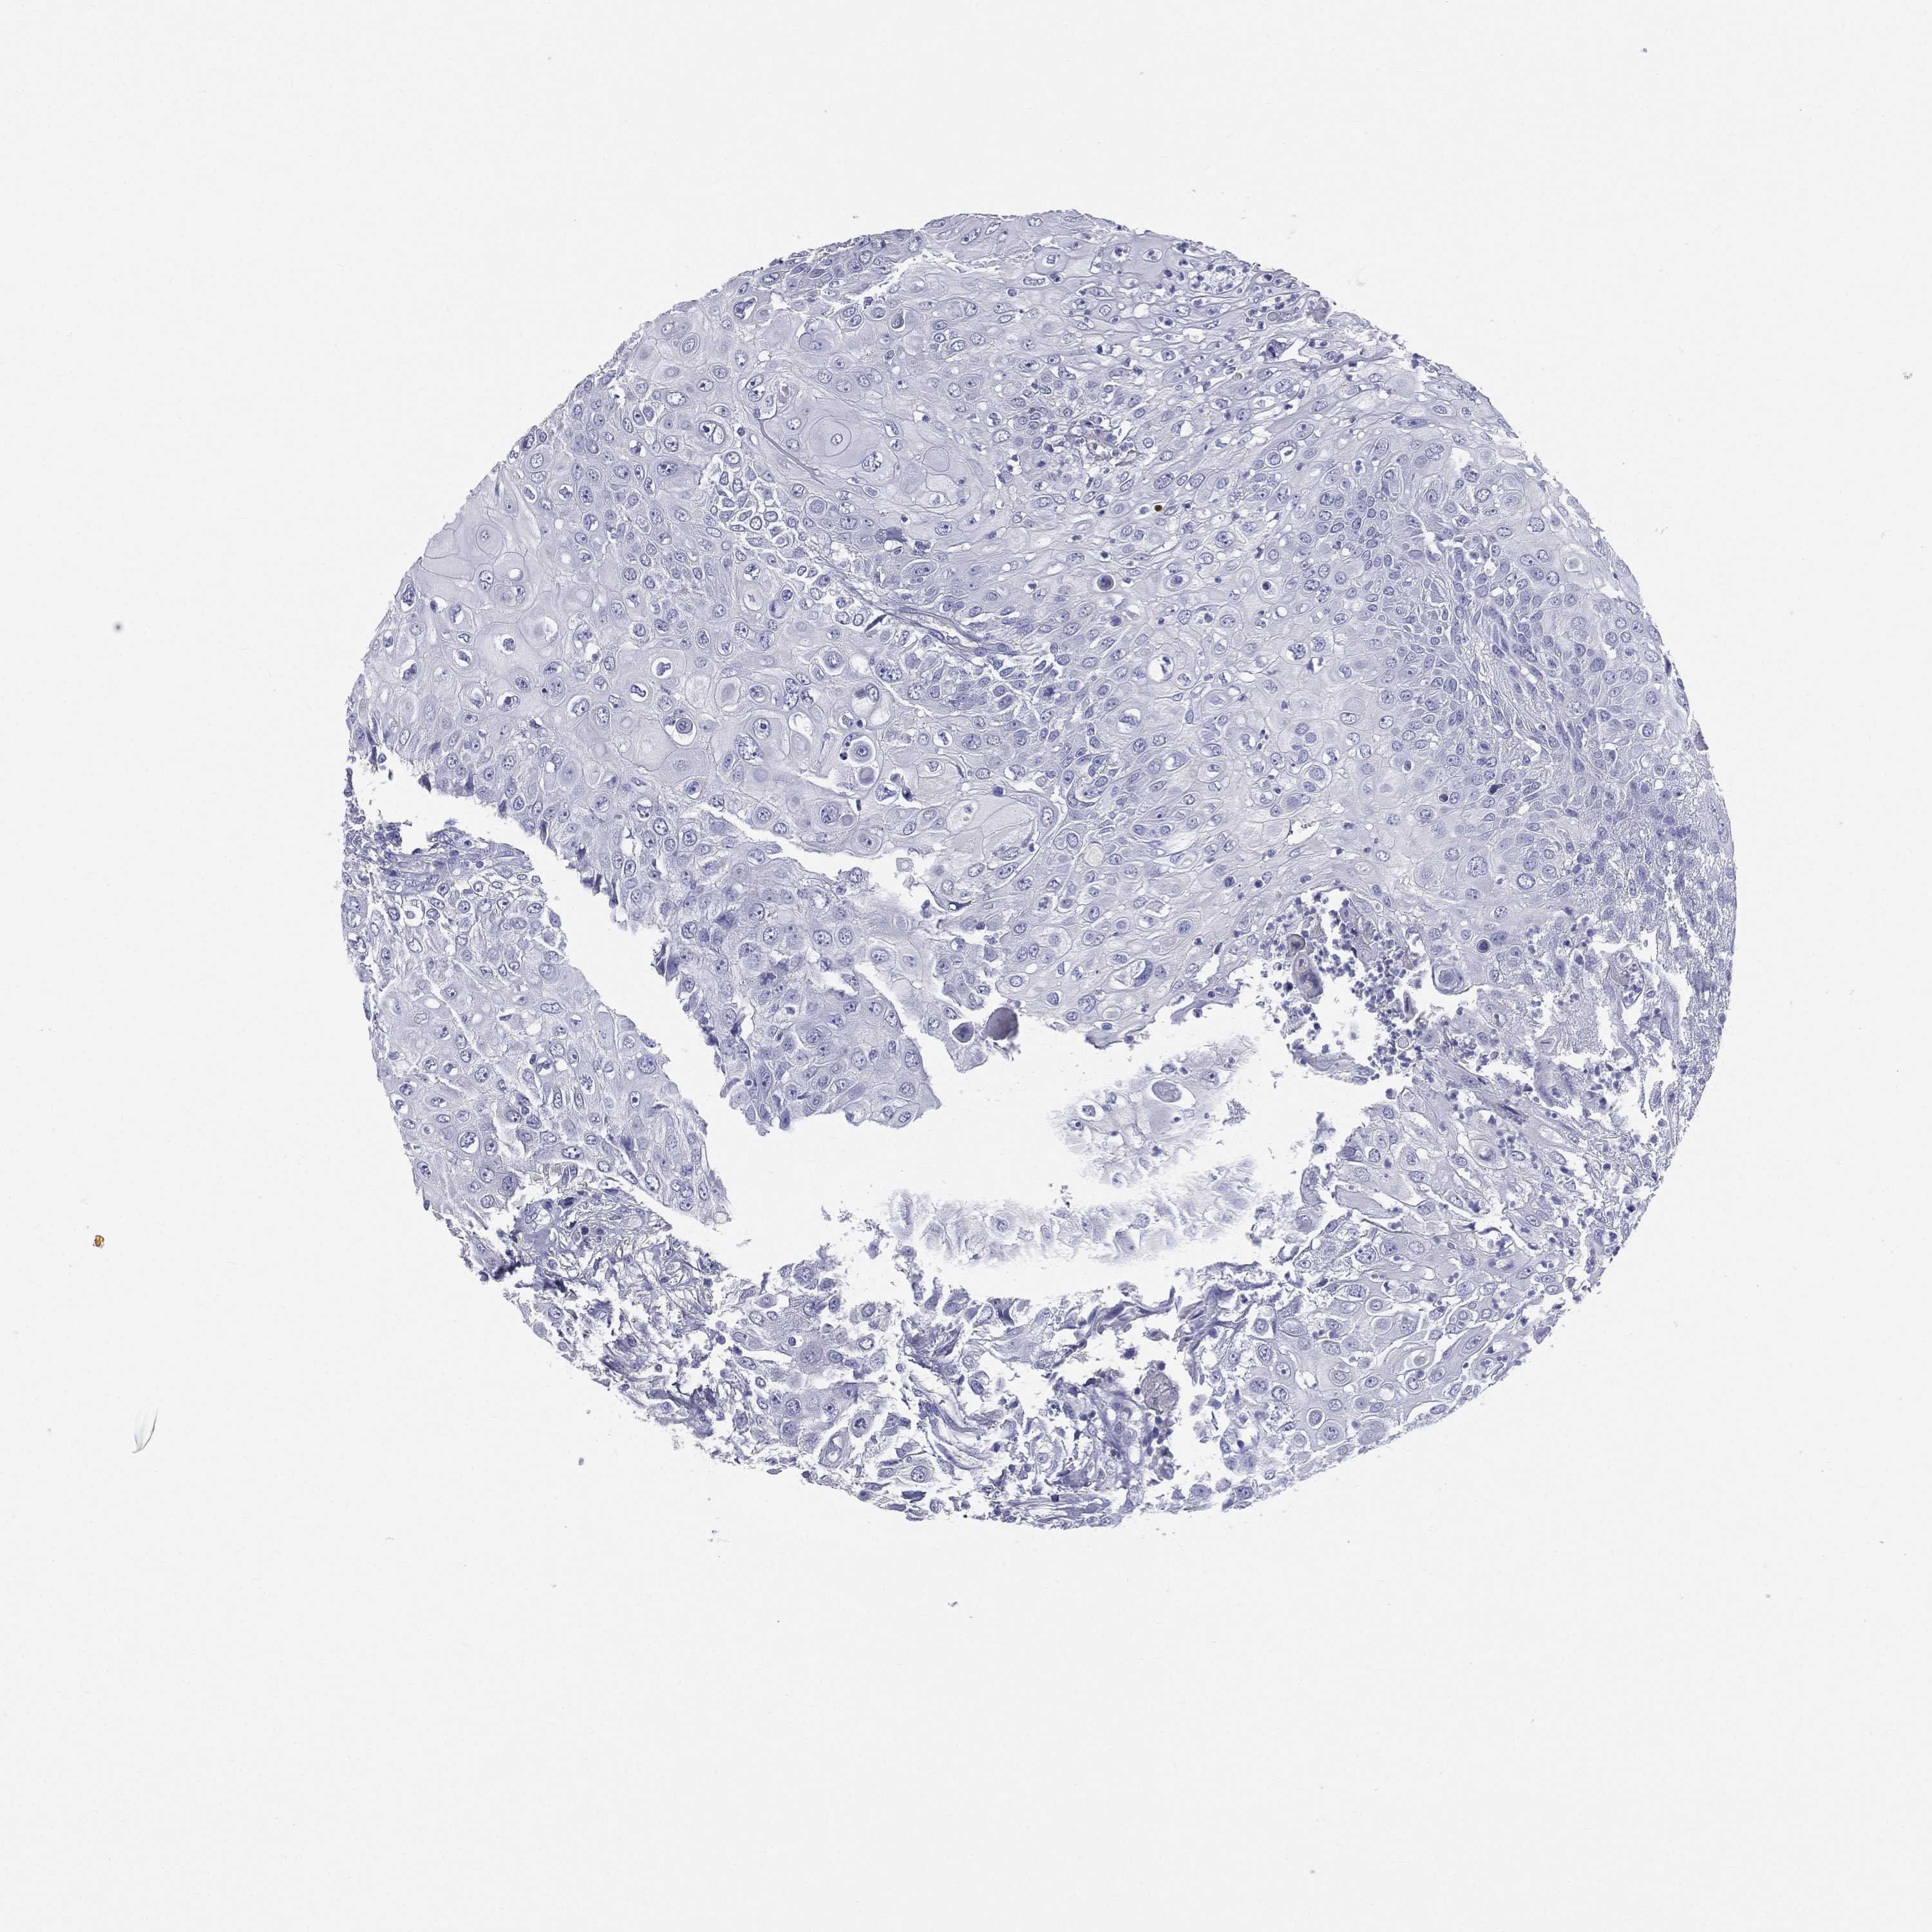

UROTHELIAL CANCER - Protein expressioni

A mouse-over function shows sample information and annotation data. Click on an image to view it in a full screen mode. Samples can be filtered based on level of antibody staining by selecting one or several of the following categories: high, medium, low and not detected. The assay and annotation is described here.

Note that samples used for immunohistochemistry by the Human Protein Atlas do not correspond to samples in the TCGA dataset.

Antibody stainingi

Antibody staining in the annotated cell types in the current human tissue is reported as not detected, low, medium, or high, based on conventional immunohistochemistry profiling in selected tissues. This score is based on the combination of the staining intensity and fraction of stained cells.

Each image is clickable and will lead to virtual microscopy that enables deeper exploration of all samples and also displays staining intensity scores, fraction scores and subcellular localization as well as patient and tissue information for each sample.

Antibody HPA047750

Antibody HPA066795

Antibody CAB003787

Urothelial carcinoma, High grade

Urothelial carcinoma, NOS

Urothelial carcinoma, Low grade